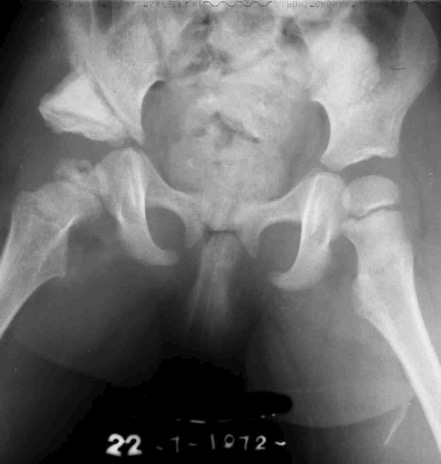

A dx risultato dopo trenta anni. La paziente lamenta dolore. Si noti l’insufficiente copertura della testa femorale

Nonostante la non perfetta sfericità della testa femorale, si esegue osteotomia periacetabolare onde migliorare la copertura della testa femorale.

Il caso fu trattato 20 anni fa.